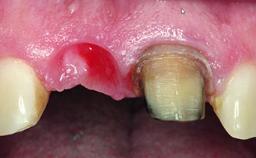

A 28-year-old patient presented at her general dentist’s office and complained about the appearance of her tooth 21. The patient had a history of trauma to this tooth. Endodontic treatment had been performed in the past and a crown placed on the tooth. A procedure to replace the old crown was performed by her dentist; however, a perforation on the middle third of the root occurred, and extraction of tooth 21 was suggested. Upon clinical and radiographic examination of the patient, who had been referred to us, replacement of tooth 21 by a dental implant appeared to be indicated.

Soft Tissue Grafting Staged